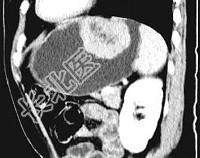

- 单项选择题女,51岁, 上腹部隐痛不适,CT检查如图, 可能的诊断是  (    )

- A、胃癌

- B、胃息肉

- C、胃腺瘤

- D、胃溃疡

- E、胃间质瘤